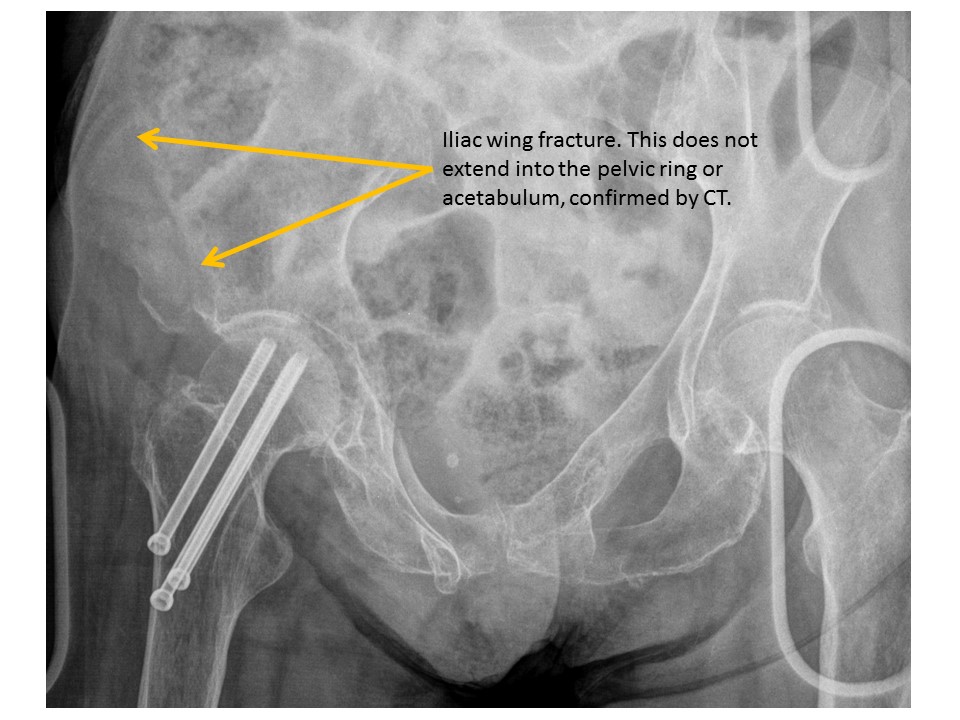

ILIAC BONES

Iliac wing fractures are present.

[Yes/No]